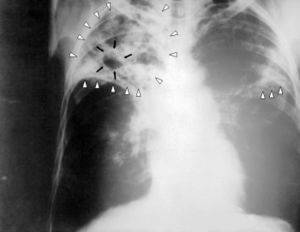

1. Рентгенологическое исследование грудной клетки. Если на снимке видны затемнённые участки, то это говорит о наличии воспалительного процесса; об эмболии легочной артерии; о раке лёгкого. Если на снимке видно, что форма тени сердца изменилась — это говорит о сердечных нарушениях.

Кашель с кровью или кровохарканье, с медицинской точки зрения, это выделение любого количества эритроцитов из бронхов или легких. Кровь в мокроте появляется при бронхите, пневмонии, бронхоэктатической болезни, туберкулезе и других опасных для жизни состояниях, поэтому больному рекомендуется немедленно начать обследование, для выявления причины возникновения кровохарканья.